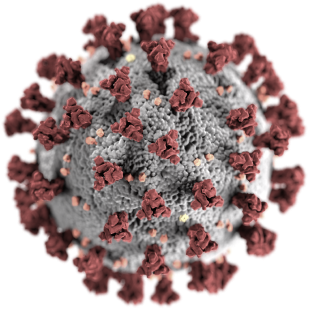

Симптомы: повышенная температура тела, утомляемость и сухой кашель. Вирус способен поражать различные органы через прямое инфицирование или посредством иммунного ответа организма. Наиболее частым осложнением является вирусная пневмония, способная приводить к острому респираторному дистресс-синдрому и последующей острой дыхательной недостаточности, при которых чаще всего необходимы кислородная терапия и респираторная поддержка. В число осложнений входят полиорганная недостаточность, септический шок и венозная тромбоэмболия.

COVID-19 — потенциально тяжёлая острая респираторная инфекция, вызываемая коронавирусом SARS-CoV-2 (2019-nCoV). Представляет собой опасное заболевание, которое может протекать как в форме острой респираторной вирусной инфекции лёгкого течения, так и в тяжёлой форме.

Симптомы: повышенная температура тела, утомляемость и сухой кашель. Вирус способен поражать различные органы через прямое инфицирование или посредством иммунного ответа организма. Наиболее частым осложнением является вирусная пневмония, способная приводить к острому респираторному дистресс-синдрому и последующей острой дыхательной недостаточности, при которых чаще всего необходимы кислородная терапия и респираторная поддержка. В число осложнений входят полиорганная недостаточность, септический шок и венозная тромбоэмболия.